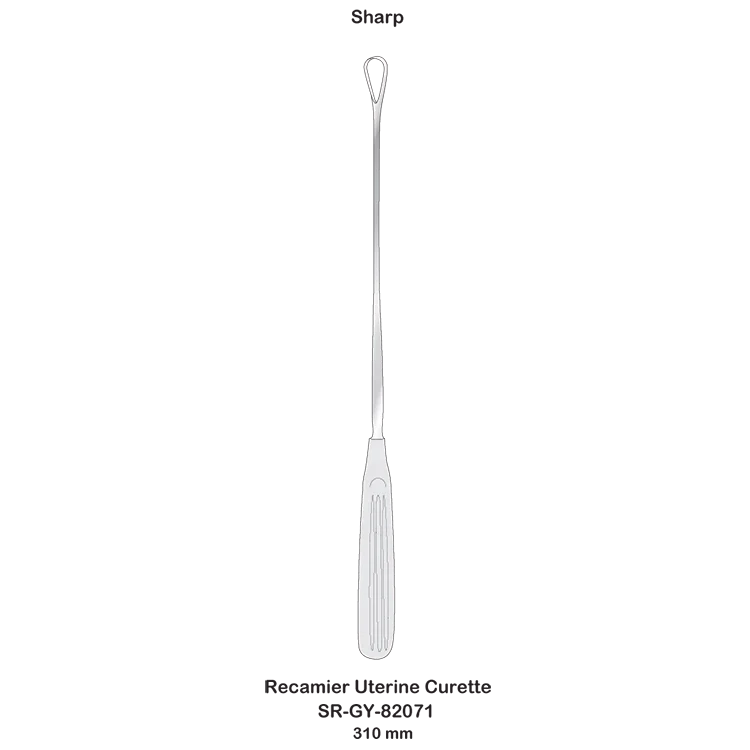

Recamier Uterine Curettes gynecological obstetric high quality surgical instruments

- Category:

- Supplier: SURGI,RANGE,CORPORATION

In Stock